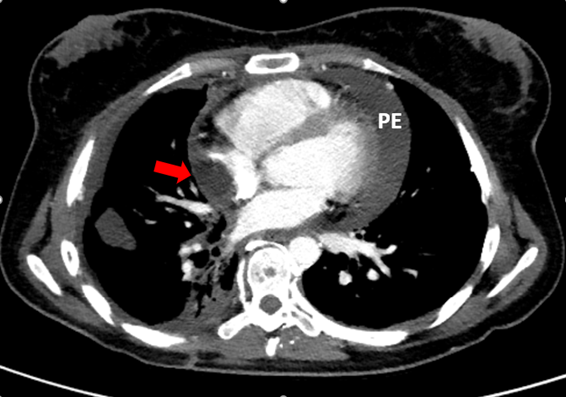

Because of the acute onset of respiratory symptoms, considering the possible diagnosis of pulmonary thromboembolism, a chest CT angiography was performed. The CT findings demonstrated signs of previous surgical manipulation of the chest, the presence of left brachiocephalic vein thrombosis, associated with intense collateral circulation, more evident in the left side. There were also sparse consolidations of the pulmonary parenchyma, azygos vein ectasia and its arch and large pericardial effusion. In the right atrium, there was a hypoattenuating rounded formation with well-defined limits, adjacent to the lateral wall (Figure 1). Considering this set of imaging findings, the patient's clinical presentation and historical status, the hypothesis was that the image seen in the right atrial chamber could represent a large thrombus, with no signs of pulmonary thromboembolism. In conjunction with the medical team, it was decided to pursue further investigation and evaluation of the repercussions of the findings on cardiac function. The echocardiogram performed the day after the CT, confirmed the extensive circumferential pericardial effusion, with signs of restriction of the ventricular filling, determining bulging of the right atrial roof and the right ventricular free wall, associated with tachycardia (108 bpm). There were no signs of thrombi or vegetations inside the cardiac chambers (Figure 2). As a consequence of that, a relief pericardiocentesis was done, draining 400 mL, with significant improvement of the clinical symptoms. After that, whole-body magnetic resonance imaging was performed during hospitalization for oncological follow-up (Figure 3), confirming the resolution of the pericardial effusion and no evidence of endocardial tumors.

Figure 1 Chest CT scan demonstrating a large pericardial effusion (PE) and a hypoattenuating rounded formation with well-defined limits, adjacent to the lateral wall, in the right atrium (red arrow).